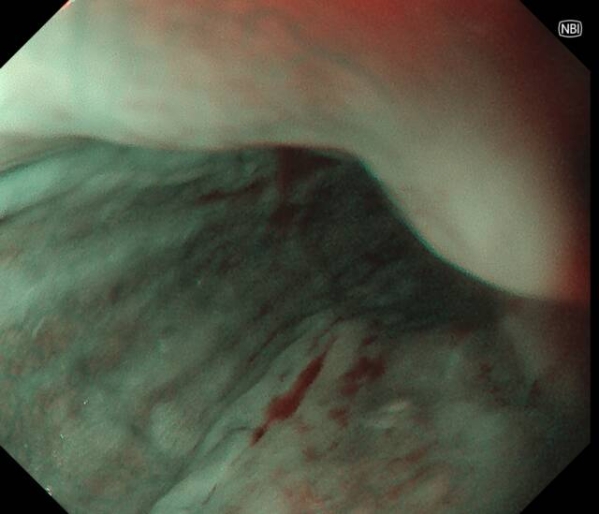

患者李先生(化名),60多岁,平日不抽烟不喝酒,无任何消化道症状,但有家族史,在子女的带领下来做胃肠镜精查。前两年刚做过胃肠镜,未发现异常。在新镜界精查中,发现胃角处有一黏膜与正常略微不同,经NBI+放大内镜放大观查,考虑胃早癌,活检证实为高级别上皮内瘤变。恰逢麻兴华教授(新镜界日方特聘专家)来院坐诊,于是由麻教授带领内镜团队行内镜下黏膜剥离术(ESD),术后患者痊愈。

因为是早期胃癌,在内镜下行黏膜剥离术(ESD),就能够治愈,无需外科手术及放化疗。这是不幸中的万幸,患者今后只需定期胃镜复查即可。